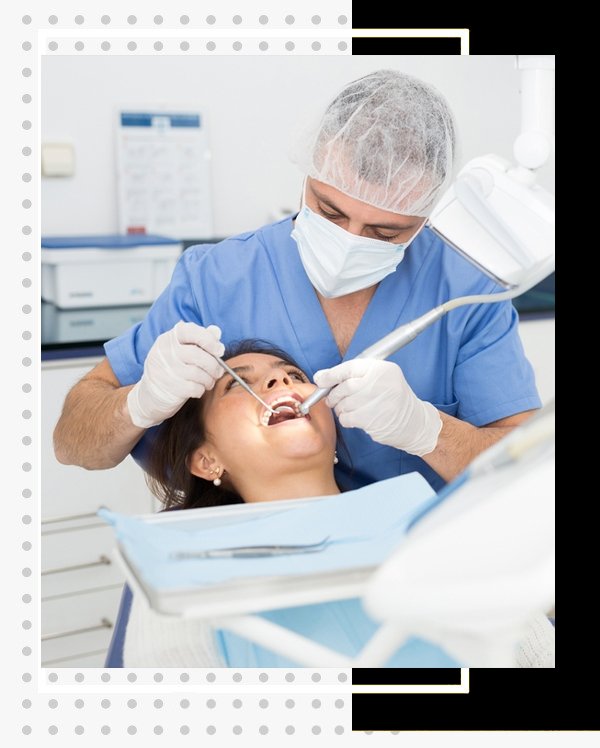

Comfort Smiles, located in Sector 41, Noida, we understand that small imperfections in your teeth can affect your confidence and smile. Our Composite Bonding treatment is a quick, minimally invasive, and highly effective solution to repair chips, gaps, discoloration, or uneven teeth, giving you a flawless, natural-looking smile.

Composite bonding uses a high-quality tooth-colored resin that is carefully applied and sculpted onto your teeth to restore shape, size, and appearance. The material bonds strongly to your natural tooth, providing a durable and aesthetic solution that blends seamlessly with the surrounding teeth.

Our expert dental team at Comfort Smiles prioritizes precision, patient comfort, and natural results. The procedure typically requires a single visit, making it a convenient and efficient cosmetic solution. Each treatment begins with a thorough dental examination and personalized plan to ensure the final outcome complements your facial features and smile.

Conveniently located in Sector 41, Noida, Comfort Smiles combines modern dental technology with a compassionate approach, ensuring every patient feels comfortable and confident throughout the process. Our dentists guide you through every step, from consultation to aftercare, ensuring long-lasting results and improved oral health.

If you are looking for Composite Bonding in Sector 41, Noida, Comfort Smiles is your trusted destination. Book your consultation today and take the first step toward a beautiful, confident, and naturally enhanced smile that transforms your appearance and boosts self-esteem.